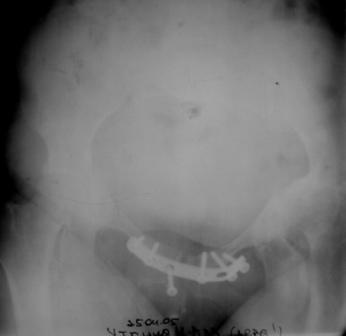

Уважаемые коллеги! Пациентка 32 года с застарелым повреждением таза, после остеосинеза лонного сочленения пластиной. Посоветуйте с выбором тактики и методик лечения.

Февраль 2004 г.

Получила травму в феврале 2004г в г.Лобытнанги ЯНАО Тюм.обл. Через неделю после поступления выполнен остеосинтез лонного сочленения пластиной. 1,5 месяца на скелетном вытяжении. В последующем ходит при помощи костылей с нагрузкой на правую ногу. Имеется нестабильность половин таза, неправильно-консолидированный перелом левой вертлужной впадины, невропатия седалищного нерва слева. В результате невропатии седалищного нерва сформировалась эквинусная установка левой стопы, парестезии по подошвенной поверхности.

Направлена к нам для устранения патологической установки стопы и эндопротезирования левого тазобедренного сустава, также имеется миграция шурупов пластины, фиксирующей лонное сочленение.

Клинически: ходит на костылях с нагрузкой на правую ногу. Левая стопа в эквинусе. Осевая нагрузка на левую н\конечность болезненна в области левого тазобедренного сустава, при прикосновениях к подошвенной поверхности стопы у пациентки чувство зжения. В левом коленном суставе полный обьем движений, в левом тазобедренном резко ограничено отведение и ротация, укорочение левой н\конечности на 2,5 см. При полипроекционной и функциональной Р-графии выявлена нестабильность левого КПС и лонного сочленения, консолидированный в порочном положении поперечный оскольчатый перелом левой вертлужной впадины с центральным смещением головки бедра. Нами выполнена коррекция деформации левой стопы. Планируется выполнить введение 2 канюлированных илиосакральных винтов слева, реостеосинтез лонного сочленения реконструктивной пластиной, после заживления ран - тотальное эндопротезирование левого тазобедренного сустава.